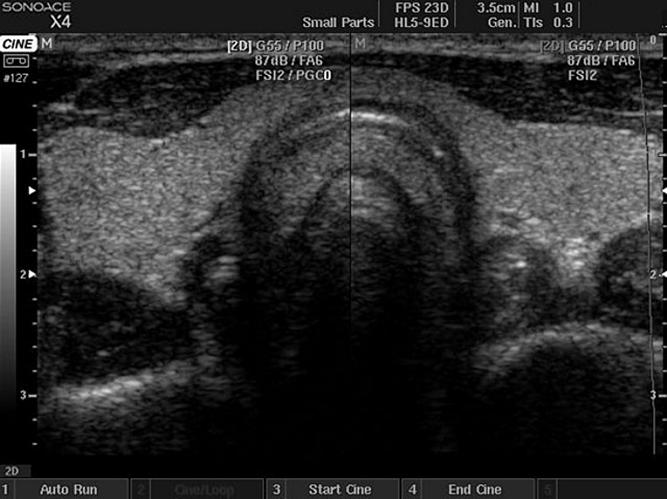

Фотографии отделения